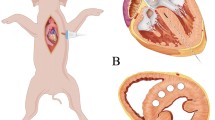

Neodymium-yttrium-aluminum-garnet laser (Nd:YAG, 800–1064 nm wavelength, 300-μm-diameter fiber, Echo Laser X4, Elesta S.R.L., Italy) was connected to an ultrasound scanner (MyLab 9.0, Esaote, Italy) for laser ablation, under the guidance of another ultrasound scanner (Acuson Sequoia 512, Siemens, Germany) with a transducer 4V1-C. In view of LV long axis, a needle (21G, PTC, ECOCHIBA, Italy) was injected into the RV obliquely from the apical area via percutaneous route, as shown in the diagram of Fig. 1a. The angle of insertion against the septum α in Fig. 1a was approximately less than 45°. The tip of the needle was inserted into the target septum along the guideline shown Fig. 1b. Note that the papillary muscle and chordae tendineae in RV were avoided under the guidance of the ultrasound during the insertion. Then, the laser fiber was inserted through the needle, and its contact with the septum was maintained. Each dog received two ablations. The first ablation was located at the basal segment of ventricular septum (avoiding the membranous segment) using a 1-W laser for 3 min (180 J). The second ablation was located at the middle segment using a 1-W laser for 5 min (300 J). Heart rate and blood pressure were recorded before and after the ablation.

a Diagram of the needle path and ablation area ((http://medmovie.com/library_id/7556/) is acknowledged), b B-mode ultrasound image showing the needle path in parasternal LV long-axis view, LV left ventricle, RV right ventricle. The angle α of insertion against the septum in Fig. 1a maintains less than 45° in the process of the insertion and ablation

Selection of the insertion path